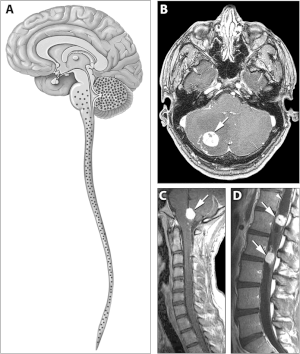

![]() | |

| Typical distribution of hemangioblastomas in Von Hippel–Lindau disease | |

Signs and symptoms associated with VHL disease include headaches, problems with balance and walking, dizziness, weakness of the limbs, vision problems, and high blood pressure. Conditions associated with VHL disease include angiomatosis, hemangioblastomas, pheochromocytoma, renal cell carcinoma, pancreatic cysts (pancreatic serous cystadenoma), endolymphatic sac tumor, and bilateral papillary cystadenomas of the epididymis (men) or broad ligament of the uterus (women).[4][5] Angiomatosis occurs in 37.2% of patients presenting with VHL disease and usually occurs in the retina. As a result, loss of vision is very common. However, other organs can be affected: strokes, heart attacks, and cardiovascular disease are common additional symptoms.[6] Approximately 40% of VHL disease presents with CNS hemangioblastomas and they are present in around 60-80%. Spinal hemangioblastomas are found in 13-59% of VHL disease and are specific because 80% are found in VHL disease.[7][8] Although all of these tumours are common in VHL disease, around half of cases present with only one tumour type.[8]